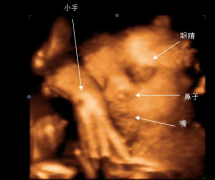

孕期做彩超检查对孕很多孕妈来说都不陌生,利用三维彩超表面成像就...

三维彩超是立体动态显示的彩色多普勒超声诊断仪,它的作用和普通的...

生个健康的宝宝是每位准妈妈最大的心愿,三维彩超不仅能够监测宝宝...